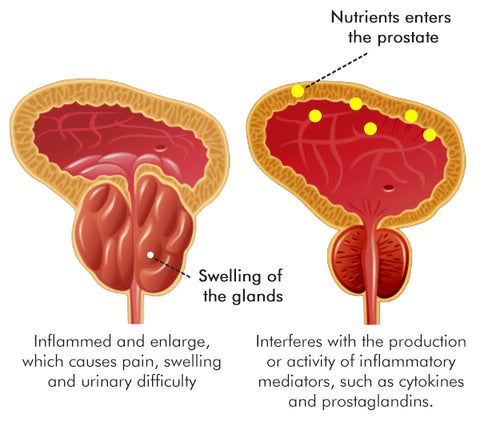

Reducing Inflammation: Prostate problems are frequently linked to inflammation within the prostate gland. The capsules contain a unique blend of natural compounds renowned for their potent anti-inflammatory properties. By targeting and reducing inflammation in the prostate, these capsules help alleviate pain, discomfort, and swelling associated with prostate issues. Interferes with the production or activity of inflammatory mediators, such as cytokines and prostaglandins. By doing so, they help modulate the inflammatory response, resulting in a decrease in inflammation and swelling.